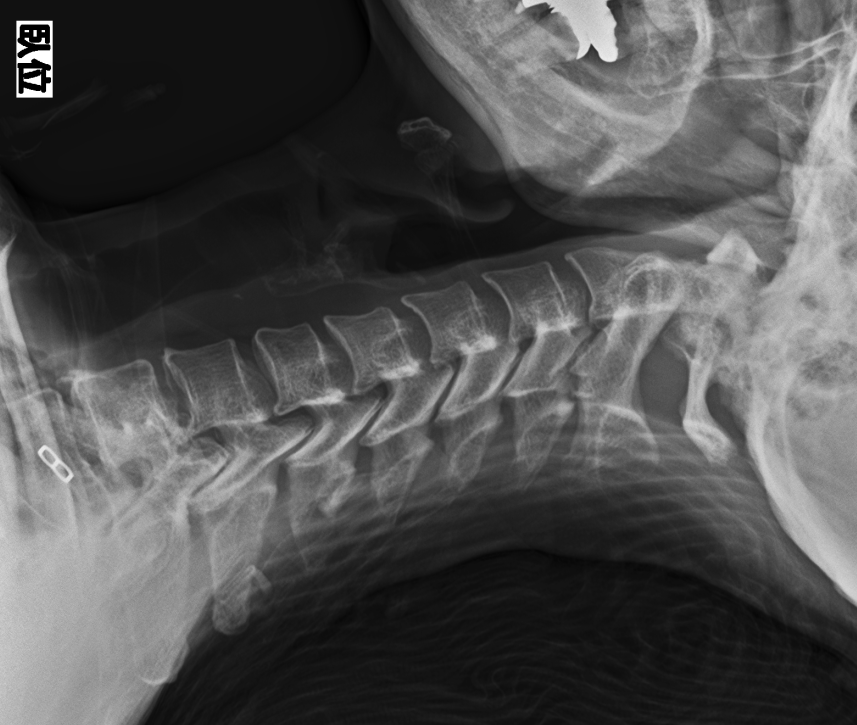

継続使用による変化の一例

ネックオアシスを継続使用した方の頸椎X線写真です。

使用前後で姿勢に変化が見られることがあります。

(※これは一例であり、すべての方に同様の変化が見られるわけではありません)

症例B 使用前

症例B 6か月使用後 80代女性・猫背